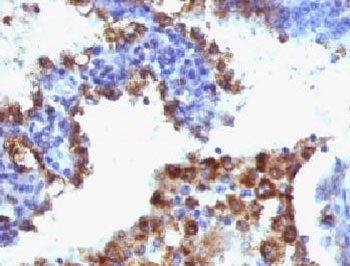

IHC: Formalin-fixed, paraffin-embedded human lung adenocarcinoma stained with Napsin-A antibody (NAPSA/1238 + NAPSA/1239).

Napsin is a pepsin-like aspartic proteinase connected with maturation of surfactant protein B. There are two closely related napsins, napsin A and napsin B. Napsin A is expressed as a single chain protein. Immunohistochemical studies revealed high expression levels of napsin A in human lung and kidney but low expression in spleen. Napsin A is expressed in type II pneumocytes and in adenocarcinomas of lung. The high specificity expression of napsin A in adenocarcinomas of lung is useful to distinguish primary lung adenocarcinomas from adenocarcinomas of other organs.